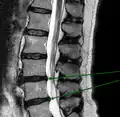

L'imagerie par résonance magnétique peut montrer la hernie, le canal vertébral, les nerfs, les tissus environnants. Les tissus mous sont les mieux analysés par cet examen qui est le plus performant pour le diagnostic de hernie discale. Les images pondérées en T2 montrent clairement la hernie.

IRM lombaire sagittale montrant des protrusions discales.